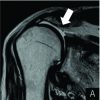

On examination, diffuse tenderness and swelling were present over bilateral shoulder with bony crepitus. No distal neurovascular deficit was noted. No other injuries were noted during the examination. Immobilization and analgesics were given in an emergency. Plain radiographs followed by computed tomography scans revealed bilateral Neer [4] IV part fracture with anterior shoulder dislocation (Figs. 1, 2). The patient was prepared for operative intervention and necessary investigations were done. Both the shoulders were operated in a single sitting. The same deltopectoral approach was used bilaterally and open reduction with Proximal Humerus Interlocking Osteosynthesis (PHILOS) plating was done (Fig. 3). The right side was operated first for no particular reason, taking approximately 3 h followed by the left side in the next 2 h. Re-draping was done and a shot of an intravenous antibiotic was given before starting the left side. Intraoperatively, a bony Bankart lesion in the right shoulder was noticed which led to persistent instability even after fixation of the proximal humerus. Henceforth, a Latarjet procedure was done for the same.